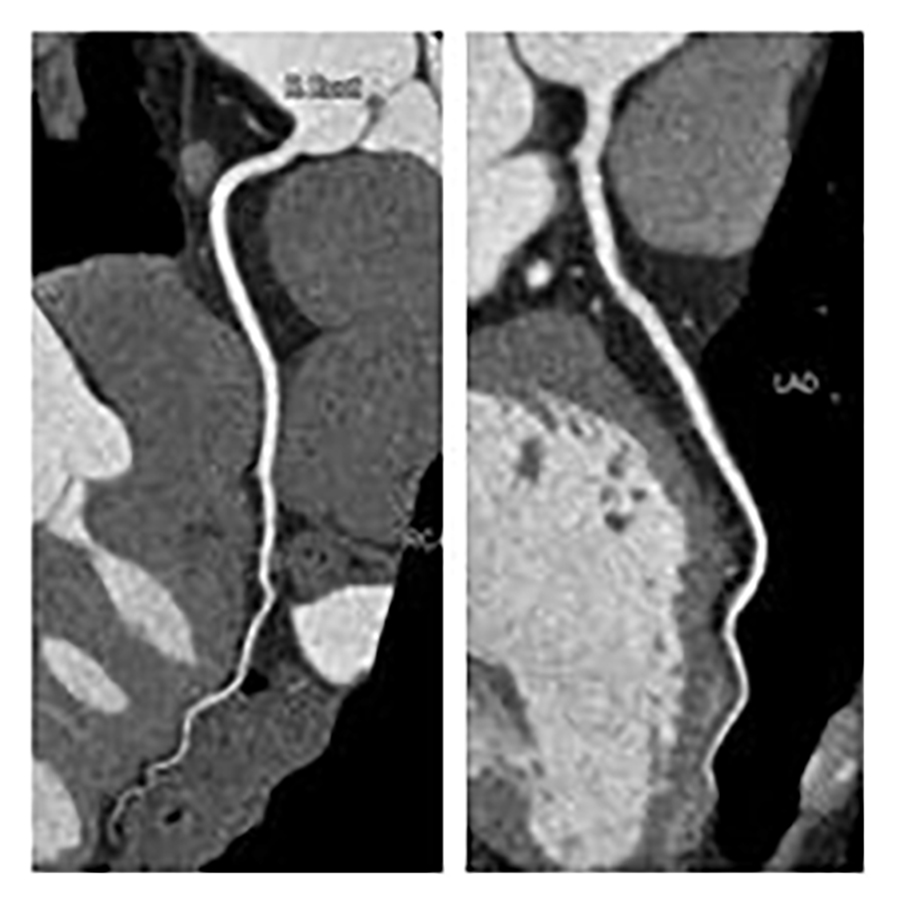

自動注入器を使用して静脈からヨード造影剤を注入し、撮影することにより血管や臓器にコントラストを付け、より詳細な情報を得る事ができます。血管精査目的の検査ではこの装置の特徴である画像ノイズ低減処理や高速撮影により造影剤の量を従来の装置より減らしながら従来の装置と変わらない画像を提供することができます。

冠動脈の石灰化や虚血性心疾患、先天性の血管走行異常など早期に発見することができます。320列CTで撮影することで、撮影時間は約1/20に、被ばく量は約1/4まで軽減できます。不整脈や息止め不良に強く、ベッドを移動させずに継ぎ目なく一度で撮影した画像なので、ミスレジストレーション(画像処理時の誤差によって生じる画像劣化)のない極めて高品質な画像を得ることになります。1心拍を最初から最後まで連続撮影することで3D画像に時間軸が加わり4D画像も作成可能となりました。